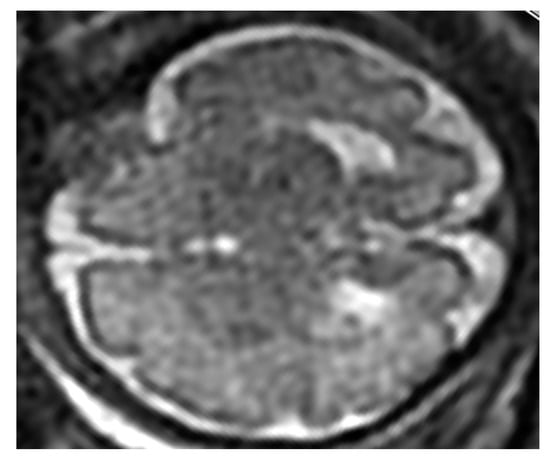

3.2.4. Disorders of Neural Migration and Proliferation

Lysencephaly

Schizencephaly

Microcephaly